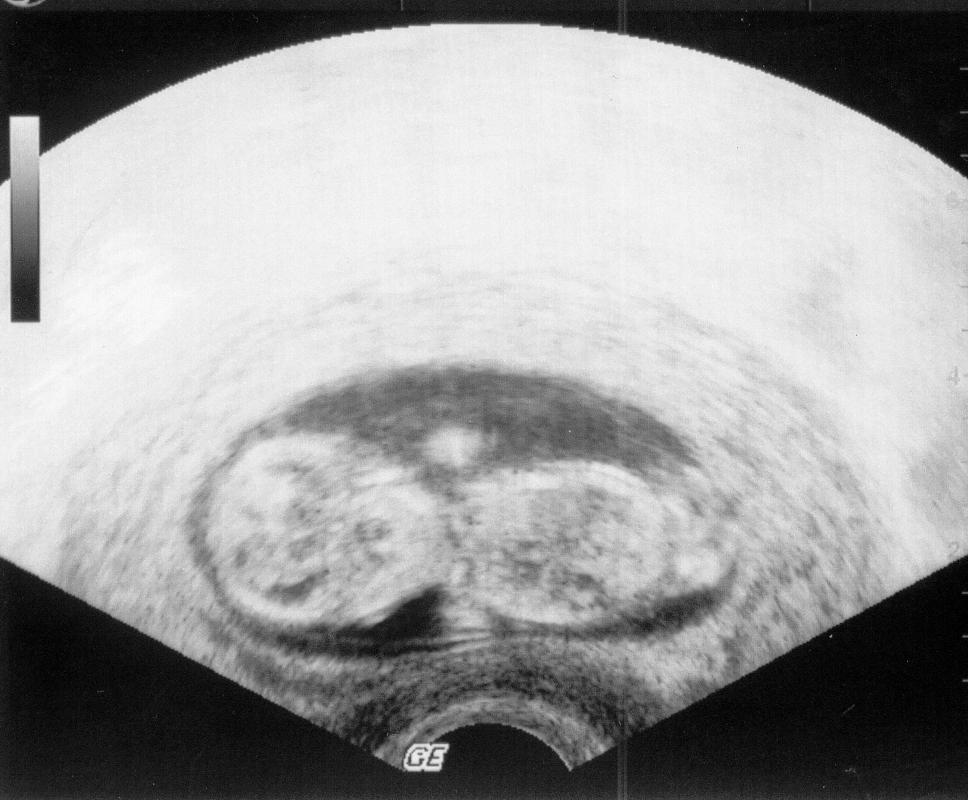

Ich habe heute am Rande mitbekommen, dass die Paare für die künstliche Befruchtun künftig keinen Trauschein mehr benötigen ?